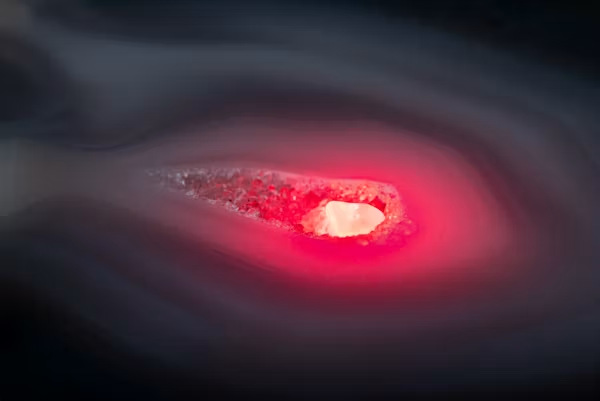

TÜTÜN KULLANIMI BEYİN KORTEKSİNDE İNCELMEYE NEDEN OLUYOR

Bilkent Şehir Hastanesi Nöroloji Uzmanı Doç. Dr. Görkem Tutal Gürsoy, tütün kullanımının yalnızca akciğerleri değil, beyin sağlığını da ciddi şekilde etkileyebildiğini belirterek önemli uyarılarda bulundu. Uzmanlara göre sigara kullanımı, düşünme,…